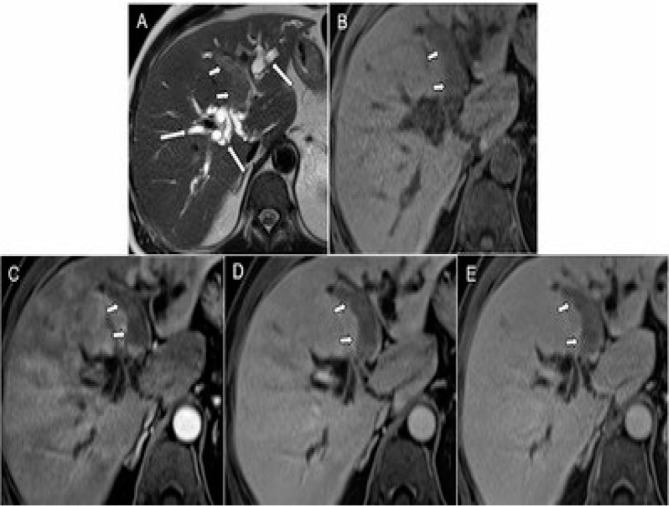

Abstract Image